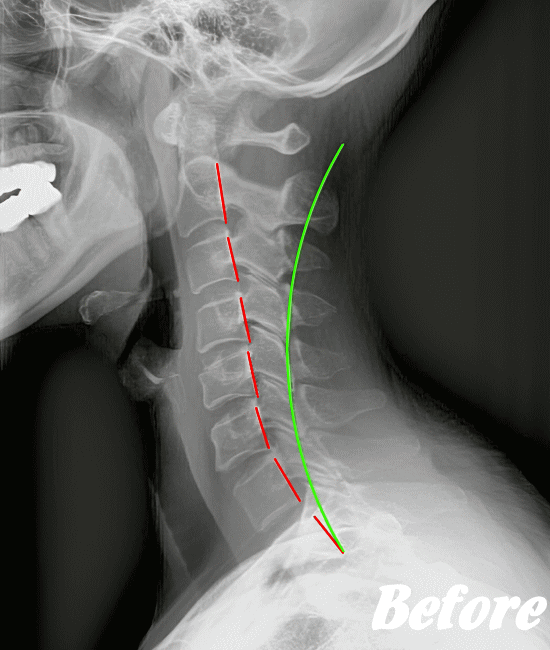

ストレートネックも、首に負担がかかりやすいので、注意が必要です。

病院では、まず問診票で首こり状態を診断します。症状により、レントゲンやCT、MRI、血液検査などを行います。特に他の病気の可能性が見つからないようであれば、頚性神経筋症候群と診断するようです。